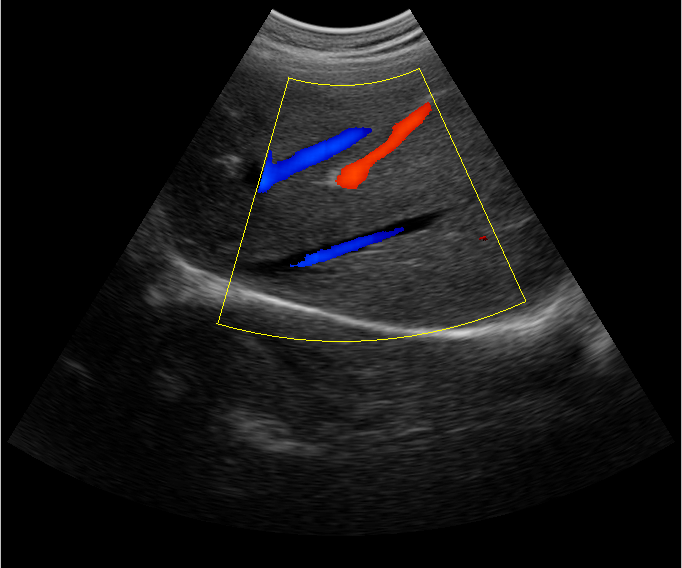

B超檢查主要是檢測肝臟的外形、大小、膽囊、門靜脈、回聲粗線等問題。由于乙肝病毒造成肝細(xì)胞破損嚴(yán)重,肝細(xì)胞出現(xiàn)問題,發(fā)生異常外形就會改變,通過B超檢查就能很清楚的檢查出肝臟受損的程度,以及肝臟的大小是否改變,肝臟是否發(fā)展為肝纖維化、肝硬化等。還可以檢查門靜脈主干內(nèi)徑是否增寬等情況。

肝臟B超還可以通過肝臟的門靜脈、回聲粗線、膽囊等指標(biāo)來診斷病情。由于肝炎病毒長期侵害會造成肝細(xì)胞破損嚴(yán)重,肝細(xì)胞出現(xiàn)異常,肝臟發(fā)生異常時外形就會改變。通過肝臟B超檢查就能很清楚地看出肝臟的受損程度,以及肝臟的大小、形態(tài)、回聲等是否正常。有利于肝臟的疾病的正確診斷。